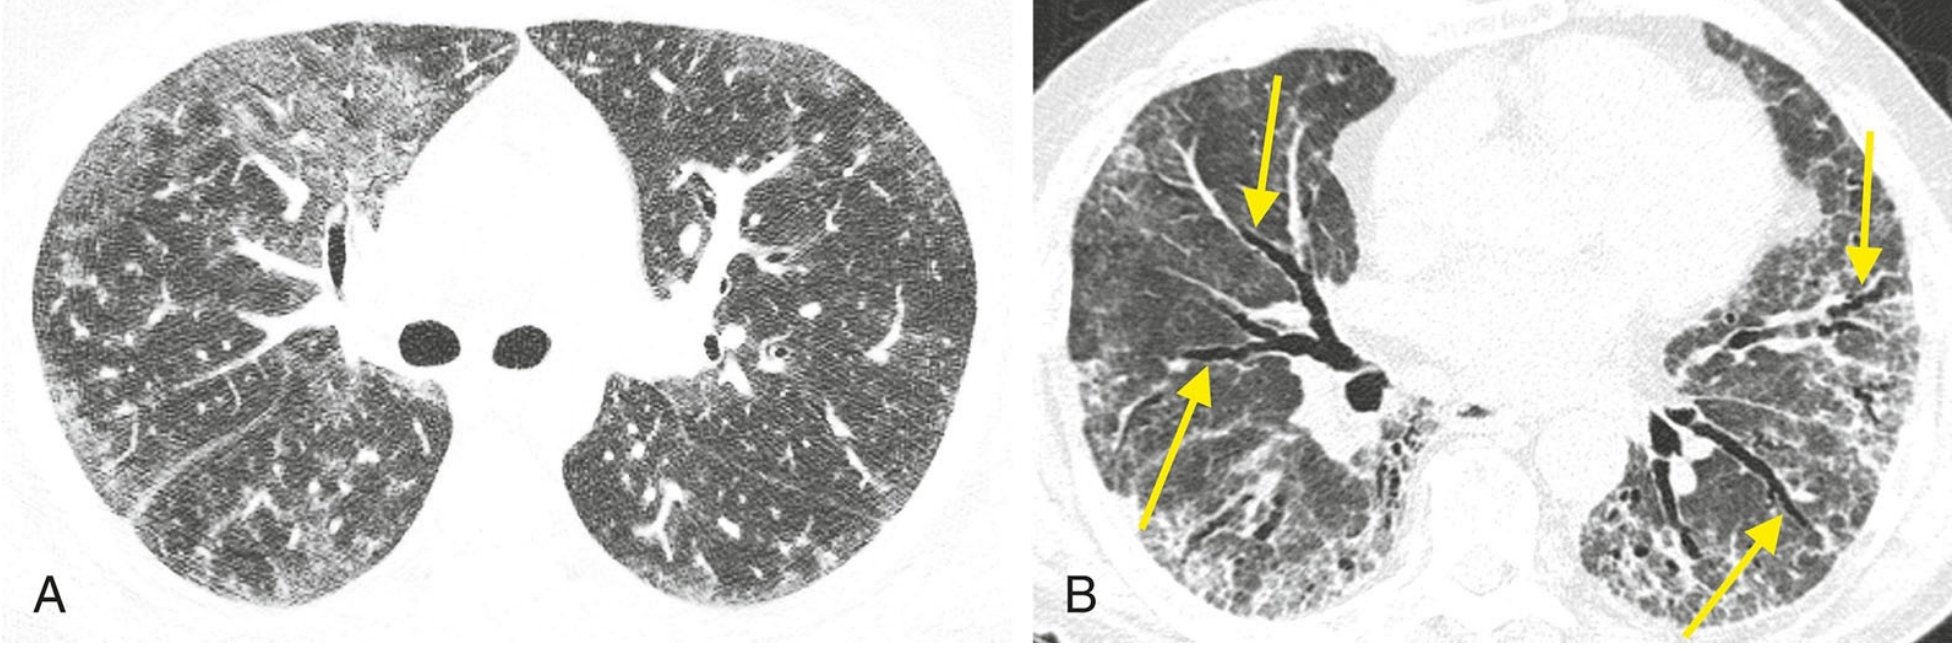

当根据HRCT表现而考虑诊断UIP模式时,鉴别诊断包括特发性肺纤维化、结缔组织病、石棉沉着病和药物中毒。这些疾病在HRCT上通常难以区分, 病理上可能也很难鉴别。

7331218b6857cead2350daf293806044.png

高置信度诊断为普通型间质性肺炎(UIP)的鉴别诊断。

4例UIP的HRCT表现;继发于特发性肺纤维化(A)、结缔组织病(B)、石棉沉着病(C)和药物中毒(D)的UIP, 均可见胸膜下及肺基底分布为主的纤维化伴蜂窝征。当表现为UIP模式时,上述疾病在HRCT上通常无法鉴别。